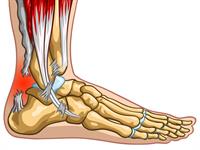

Saišu sastiepums. Locītavas ir kustīgi skeleta kaulu savienojumi. Saites savieno locītavu veidojošo kaulu galus un notur tos attiecīgā stāvoklī. Tās nav elastīgas, tāpēc tās iespējams sastiept vai pārraut.

Potītes sastiepums

Saišu plīsums